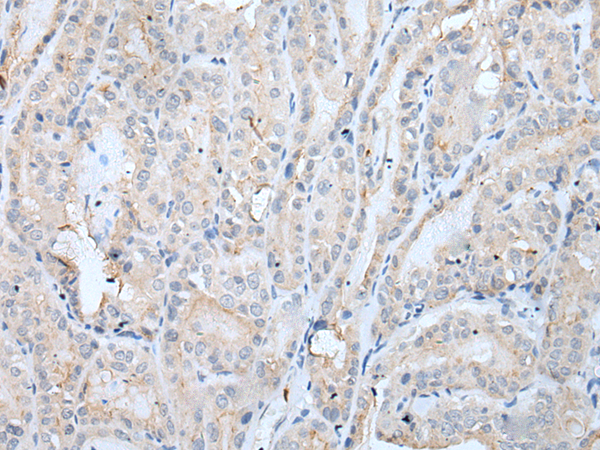

分类: 科研抗体货号: P12782别名: DEL5q14.3; C5DELq14.3应用: IHC反应种属: Human, Mouse